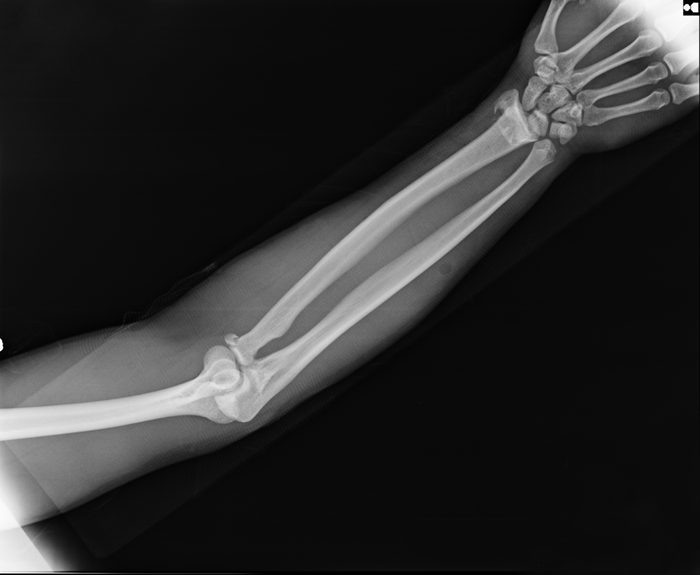

X-ray view of elbow

Tushchakorn/Shutterstock

The disease that turns your tissue into bone

Fibrodysplasia ossificans progressiva (FOP) is in the running for the most common disease on this list; about 1 in 2 million people have been diagnosed with it, according to the NIH. It is a genetic disorder that transforms soft tissues into bone after injury or other trauma. Eventually, the disease can cause joints and muscles to stiffen up and fuse together. Like many of the other rare conditions on this list, there is currently no known cure.